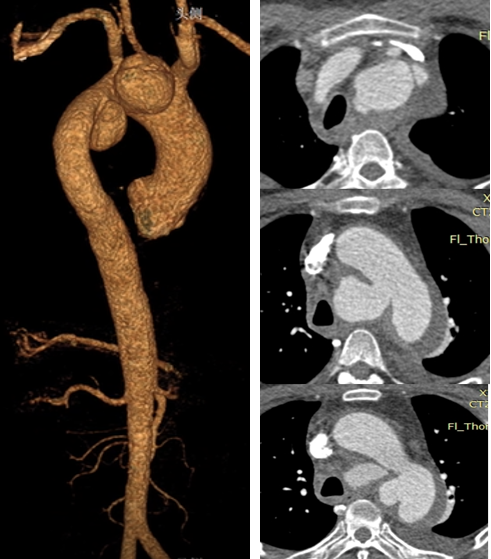

韩某,男,53岁,“查体发现主动脉弓部溃疡15天”入院,主动脉CTA提示:主动脉溃疡(弓部);2. 主动脉壁内血肿。患者高血压病史8年,最高210/130mmHg,无规律服药。

术前 CTA

术前

术后

手术用时115分钟